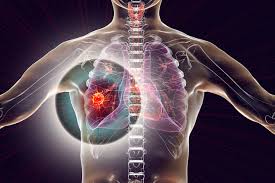

What Are Symptoms Of Lung Cancer In Humans / World Lung Cancer Day 2018 12 Early Signs And Symptoms Of Lung Cancer Health Tips And News - How long a person has smoked (or had smoked before quitting).. A tumor site located in the lung tissue or subpleural: Like many other types of cancer, lung cancer may also cause systemic symptoms, like loss of appetite or general fatigue. Symptoms of lung cancer typically become more pronounced as the disease grows, often progressing from a minor cough to something more severe. So if you notice any symptoms or changes get them checked out by your gp as soon as. Cancer causes changes in cells that are otherwise healthy.

Discover 10 common lung cancer symptoms at 10faq health and stay better informed to make healthy living decisions. How many days does it take for the symptoms to appear after the bite? Again, many of these symptoms are more likely to be caused by something other than lung cancer. Many people with lung cancer don't have symptoms until the disease is in its later stages. So, you might wonder what are the symptoms of lung cancer. Simptom clippings rigler (place of entry of the bronchus). This growth can spread beyond the lung by the process of metastasis into nearby tissue or other parts of the body. Small cell lung cancer is named after the characteristic and structure of the cancer cells formed inside the lungs which is common for a smoker or someone who consumes a this article tells about what are the lung cancer symptoms and causes which are useful know to this dangerous health problem. Cancer causes changes in cells that are otherwise healthy. Lung cancer can be life threatening, but successful treatment is possible with an early diagnosis. The cells grow too quickly, without dying off. Still, if you have any of these problems, it's important to see your. You may not notice any symptoms of lung cancer ― many people don't.